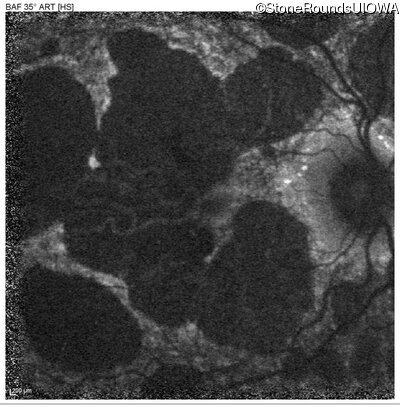

Blue Autofluorescence - Right - 20/40 -2 sc

Exemplar

Blue Autofluorescence - Left - 20/60 +2 sc